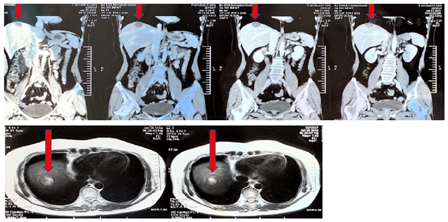

腹盆增强CT(2018年6月13日北医三院)示:肝占位病变,考虑肝转移。右侧内乳及右侧心膈角淋巴结转移(图1)。